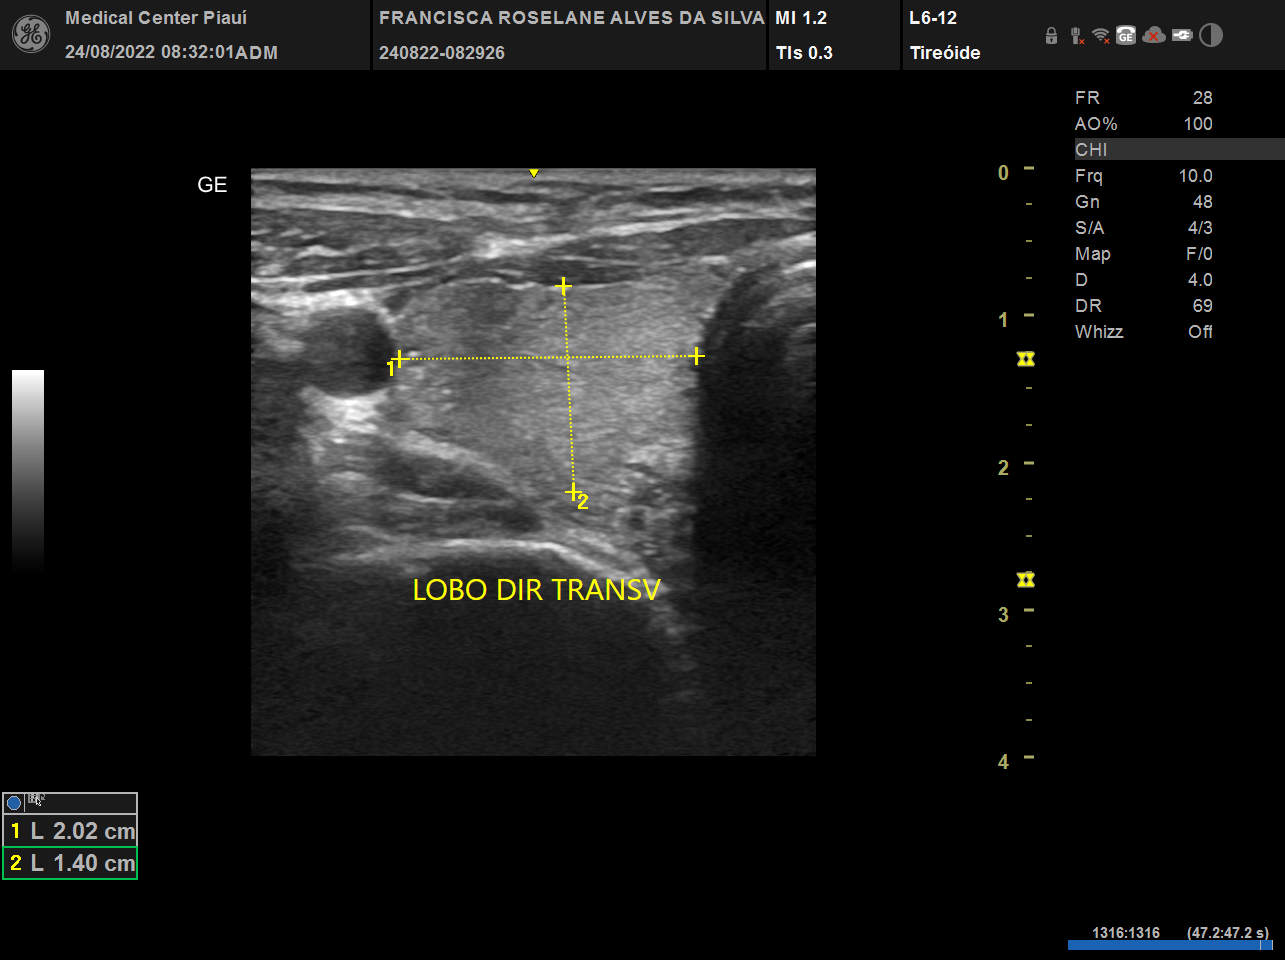

USG, TC e RN de tireoide